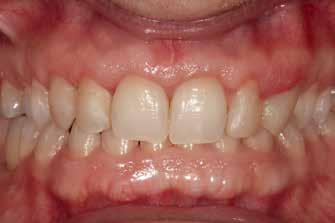

Figure 4. Placement of the unitary transepithelial after the second phase at 5 months for progressive loading of the implant.

Figures 5-6 Clinical images of the patient at the time of crown placement. Figure 7. Radiographic image at 4 years of follow-up showing the bone stability of the implant and the rehabilitation.

Figure 2 Figure 3 Figure 4 Figure 1